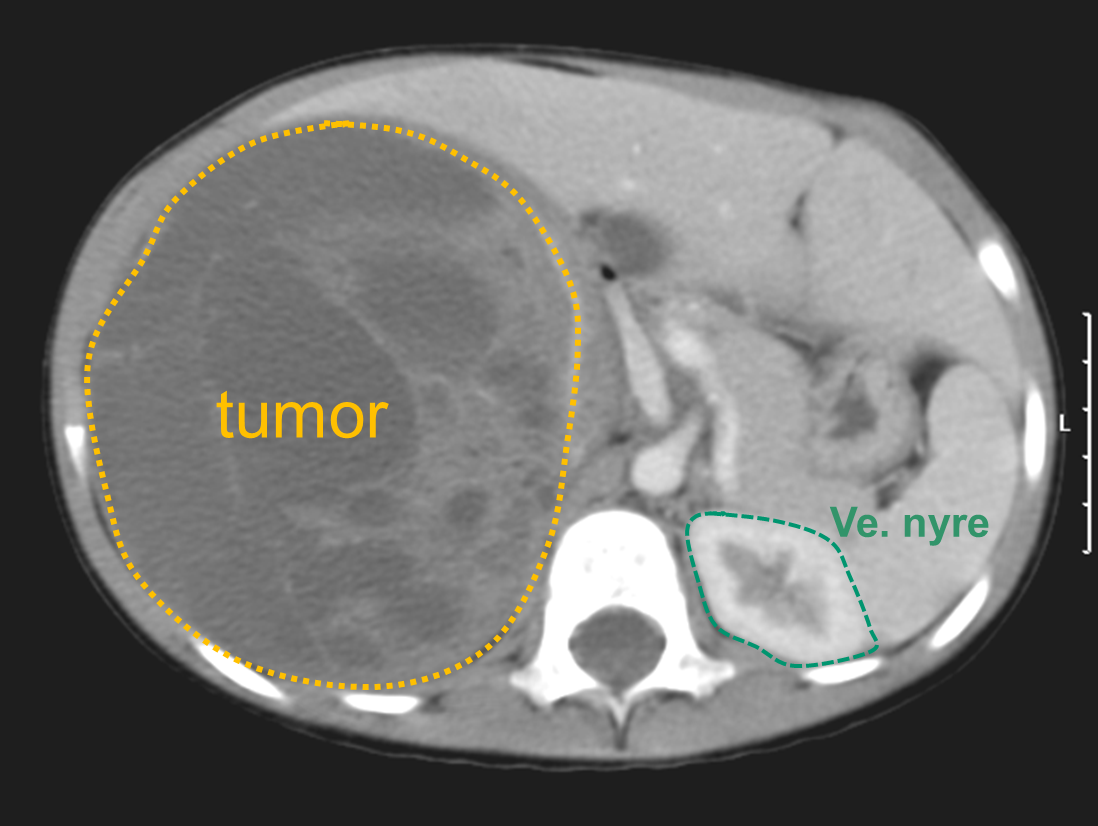

Bildet viser at Wilms tumores kan bli enorme før de blir oppdaget.

Det vanligste er at man oppdager en stor tumor i abdomen hos et lite barn. Ofte kan dette være tilfeldig oppdaget hos et ellers friskt barn. Det forekommer ellers mavesmerter, blodig urin og i sjeldnere tilfeller høyt blodtrykk. Allmennsymptomer som nedsatt matlyst eller feber er heller sjeldne.